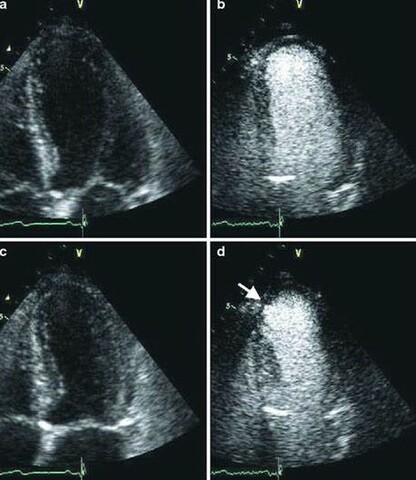

Injectable Ultrasound Enhancements

Seen in this photograph is a heart administered with a microbubble enhancement agent. These types of enhancements allow the technologist to evaluate the heart for wall motion abnormalities or blood clot formation.